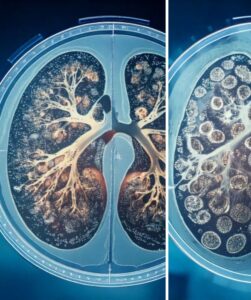

The Promise of Alveolar Regeneration

A key challenge in emphysema is the irreversible destruction of alveoli, the tiny air sacs responsible for oxygen exchange. The prospect of alveolar regeneration — the regrowth or repair of these crucial structures — is a holy grail in lung medicine. While full regeneration remains a complex challenge, ongoing studies, some of which are documented on ClinicalTrials.gov, are investigating whether MSCs or other regenerative strategies can:

- Reduce alveolar damage.

- Improve the microenvironment for existing lung cells.

- Potentially stimulate some degree of structural repair.

This is not about promising a “new lung,” but rather exploring the body’s innate capacity for repair, augmented by potential advanced pathways. The focus is on measured, incremental improvements in lung function and, most importantly, in a patient’s quality of life.